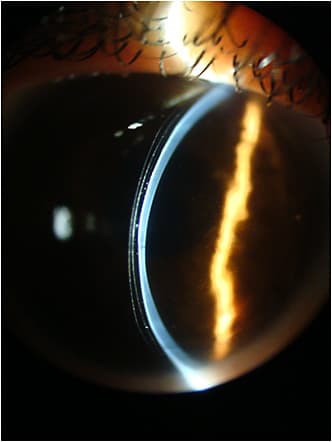

With fluorescein, we also observed superior touch at the limbus and areas in which the haptic was loose (Figures 3 and 4). The loose and the tight areas were also evident in optical coherence tomography (OCT) images. Despite this, the patient did not complain of discomfort.